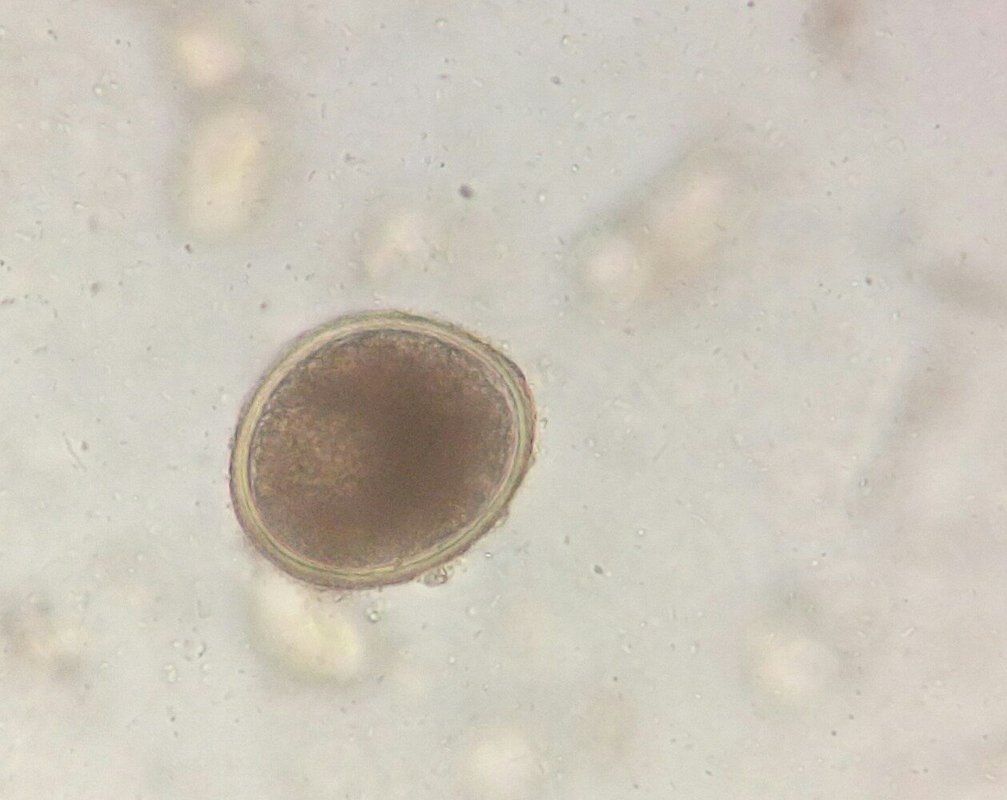

Мы также располагаем кадрами и оборудованием для проведения лабораторных анализов. Имея на руках результаты исследований, доктор будет объективен, назначая лекарства и процедуры. Это в особенности актуально при лечении животных, ведь они не имеют возможности рассказать нам о своих симптомах!

Среди наших услуг анализ крови, анализы на панлейкопению, пироплазмоз, токсоплазмоз, УЗИ, анестезия, вакцинация кошек, собак и кроликов, вакцинация против бешенства, взвешивание животных, дегельминтизация кошек и собак, кастрация, проведение кесарева сечения, купирование хвоста, обработка от блох, прием родов у животных, стерилизация, удаление зубного камня, удаление зубов, извлечение клещей, уколы, чистка зубов, услуги груминга (в том числе маникюр, подстригание когтей, стрижка и чистка ушей), эвтаназия животных, приём ветеринарного дерматолога, кардиолога, офтальмолога, стоматолога, терапевта, хирурга, гинеколога и диагноста, оформление ветпаспорта, консультация герпетолога и орнитолога, диспансеризация животных, стационар для животных, лечение грызунов, змей, морских свинок и экзотических животных.